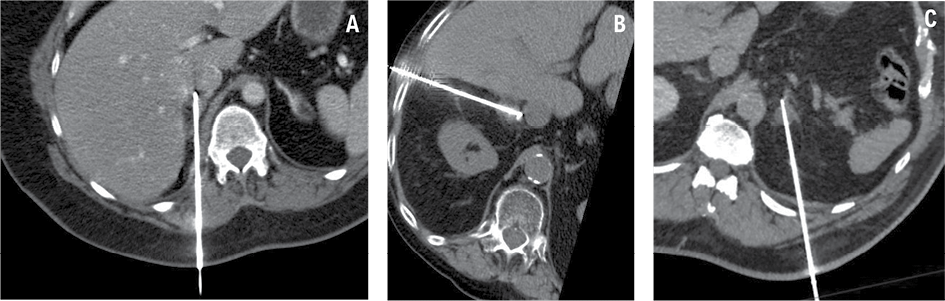

Adrenal ablation procedures were performed under general anesthesia. The patient’s positioning – either on their left side or prone – was determined by the interventional radiologist to optimize access to the adrenal lesion, based on its location and the required angle for a safe and effective approach during MWA. Native or contrast-enhanced control abdominal CT imaging was used to confirm the exact lesion location and plan the needle trajectory. Using ultrasonography (US) and CT guidance, a 14-gauge antenna was inserted through 2 mm skin incisions to target the adrenal adenoma (Fig. 2). MWA was performed at varying power settings and durations, with full details provided in Table 1. Post-procedural CT scans were then performed to assess the immediate success of the treatment and identify any potential complications.

All procedures were conducted under general anesthesia with orotracheal intubation. Patient positioning on the CT table was determined by the tumor location and laterality. Dorsal access was obtained in two cases with patients placed in the prone position, while transhepatic access was employed in one case with the patient positioned on their left side. The mean total procedure time was 91.7 minutes (range 55–120), and the mean length of hospital stay was 9.3 days (range 1.5–19).